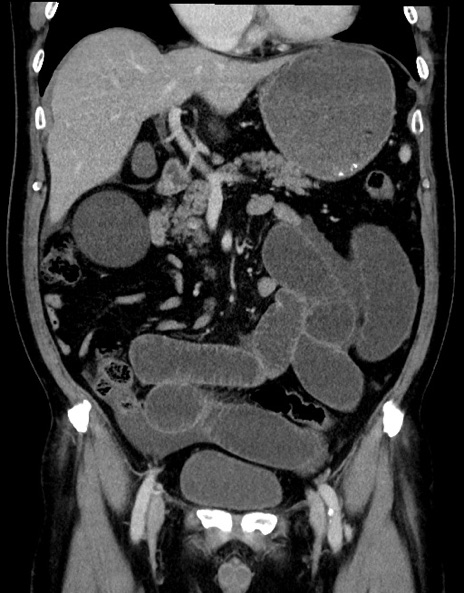

症例15(冠状断像)

【症例】70歳代男性

【主訴】腹痛

【現病歴】今朝から腹痛あり。全体的に痛い。特に左上の方。排ガスが今日はない。冷や汗が出る。

【既往歴】直腸癌術後

【身体所見】左側腹部〜上腹部に圧痛あり。腹膜刺激症状明らかなではない。軽度反跳痛。左下腹部に術後瘢痕あり。

【データ】WBC 7700、CRP 0.02